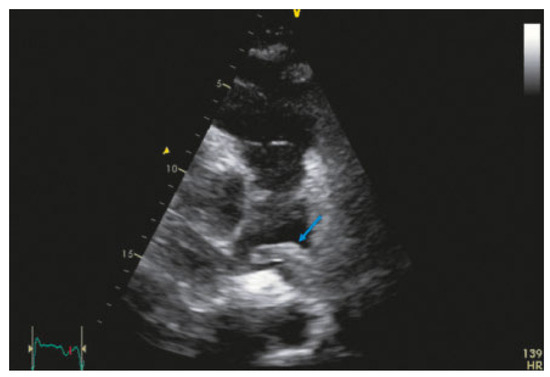

Value of Echocardiography in Differentiation of Acute Dyspnoea

by Ioannis Kapos and Felix C. Tanner

Echocardiography is one of the most effective imaging modalities for investigation of patients with acute dyspnoea. This review summarises appropriateness criteria and current guidelines for the use of cardiac ultrasound in common clinical scenarios presenting with acute dyspnoea, and illustrates such scenarios with [...] Read more.

Echocardiography is one of the most effective imaging modalities for investigation of patients with acute dyspnoea. This review summarises appropriateness criteria and current guidelines for the use of cardiac ultrasound in common clinical scenarios presenting with acute dyspnoea, and illustrates such scenarios with typical echocardiographic findings. Full article

Show Figures

Figure 1